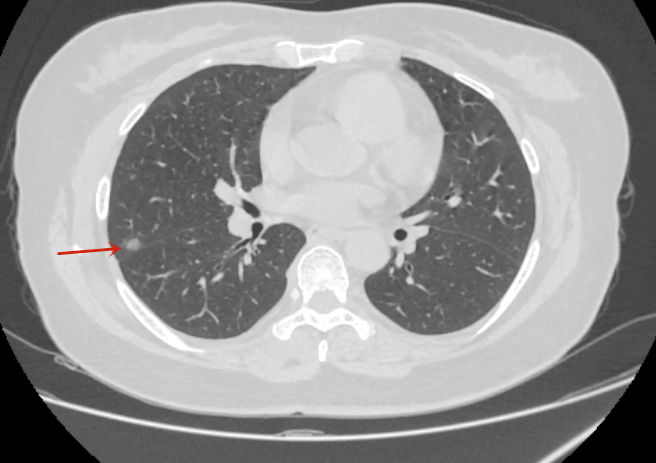

患者张女士在体检中发现右上肺多发结节结节,最大直径约1.2cm,经影像学评估后,医生建议行右上肺叶切除术。术后病理确诊为微小浸润性肺腺癌,属于早期肺癌。目前患者恢复良好,术后无需接受化疗,仅需定期复查。

▲胸部CT是右上肺、右中肺多发肺结节(箭头所示)